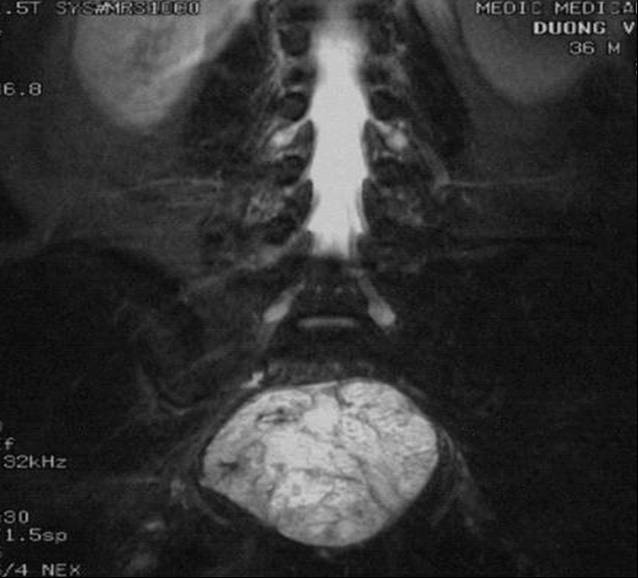

Hypersignal on T2WI